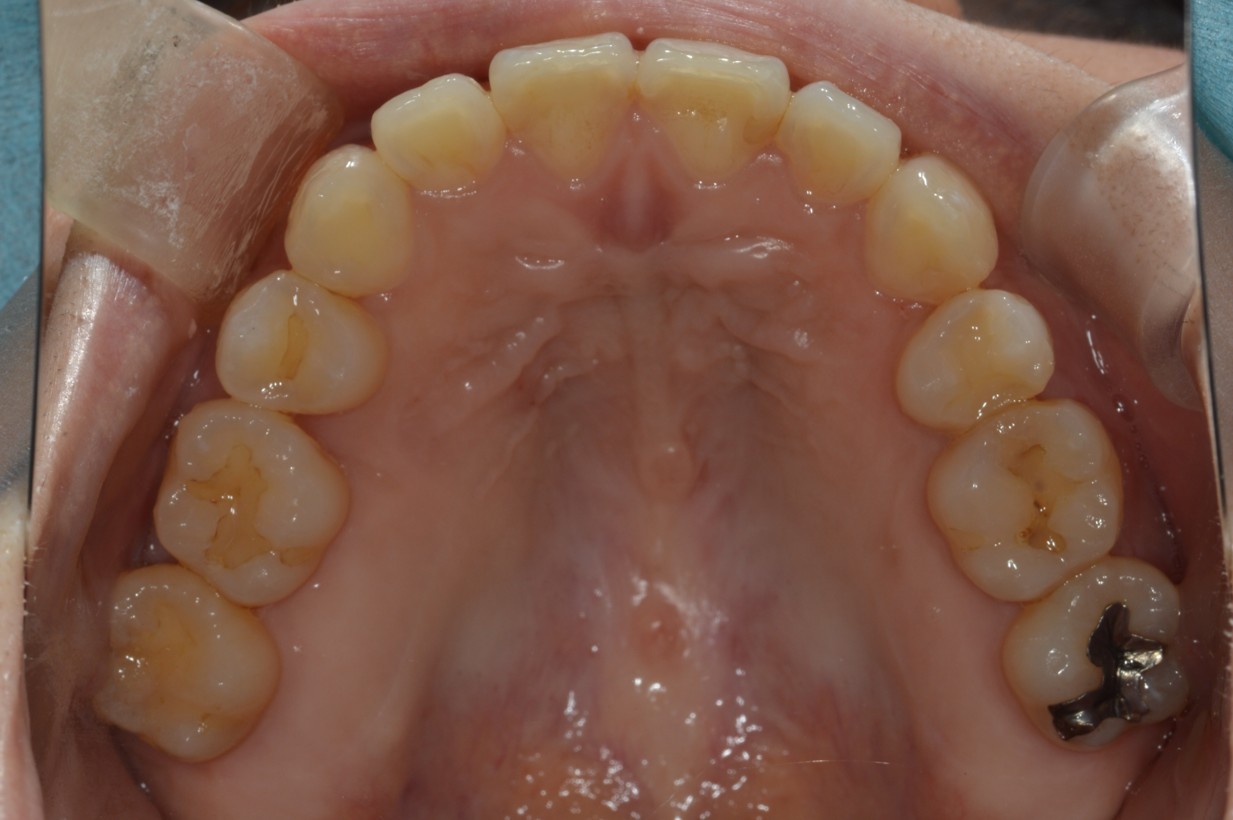

症例2

| 項目 | 詳細 |

|---|---|

| 患者様データ | 30代 女性 |

| 来院時の主訴 | 「右上の、内側に生えている歯が邪魔。」 |

| 矯正法 | 上の歯2本、下の歯2本、親知らず3本を抜歯しての矯正 |

| 通院期間 | 3年6ヶ月 |

| 治療費 | 総額:1,230,000円(税抜) 【内訳】 精密検査50,000円、メタルワイヤー矯正800,000円、月に1度の調整料5,000円、後戻り防止のリテーナー35,000円×2 |

| リスクと副作用 |

①歯を動かす事による痛みがあります。また、装置に慣れるまでは、口内炎ができやすいです。 ②歯肉が退縮するリスクがあります。装置が全ての歯に付くので、ハミガキが難しくなります。 ③長期的なメインテナンスが必要 |

| ここがこだわりのポイント!☝ | こちらの患者様は上の歯が1本内側に生えていましたが、奥歯の噛み合わせの方が問題でした。ハサミ状咬合といい、奥歯が極端に外側に向いており、下の歯と噛み合っていない状態でした。ハサミ状咬合は長期的にみると、前歯に大きな負担がかかったり、磨きにくい事による虫歯や歯周病になりやすいなどのリスクがあります。治療期間はかかりましたが、見た目の良さだけでなく、機能的にも改善しました。 |